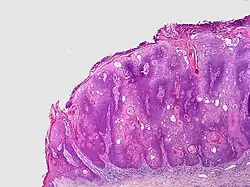

Seborrheic keratoses may be divided into the following types:[2][13][14]

| Subtype (and alternative names) | Characteristics | Image |

|---|---|---|

| Common seborrheic keratosis (basal cell papilloma, solid seborrheic keratosis) | Dull or lackluster surface.[2]: 769 | |

| Reticulated seborrheic keratosis (adenoid seborrheic keratosis) | Dull or lackluster surface, and with keratin cysts seen histologically.[2]: 769 | |

| Stucco keratosis (deratosis alba,[15] digitate seborrheic keratosis, hyperkeratotic seborrheic keratosis, serrated seborrheic keratosis, verrucous seborrheic keratosis) | Common. Dull or lackluster surface, and with church-spire-like projections of epidermal cells around collagen seen histologically.[2][3] Stucco keratoses are often light brown to off-white, and are no larger than a few millimeters in diameter. They are often found on the distal tibia, ankle, and foot.[14] | |

| Clonal seborrheic keratosis | Dull or lackluster surface, and with round, loosely packed nests of cells seen histologically.[2]: 769 | |

| Irritated seborrheic keratosis (inflamed seborrheic keratosis, basosquamous cell acanthoma) | Dull or lackluster surface.[2]: 769 | |

| Seborrheic keratosis with squamous atypia | Dull or lackluster surface, and with round, loosely packed nests of cells seen histologically.[2]: 770 | |

| Melanoacanthoma (pigmented seborrheic keratosis) | Dull or lackluster surface.[2]: 770 [3]: 687 It involves a proliferation of keratinocytes and melanocytes.[16] | |

| Inverted follicular keratosis[notes 1] | Asymptomatic, firm, white–tan to pink papules[15] Microscopically it is characterized as a well-circumscribed inverted acanthotic squamous proliferation containing squamous eddies and without significant atypia.[17] |